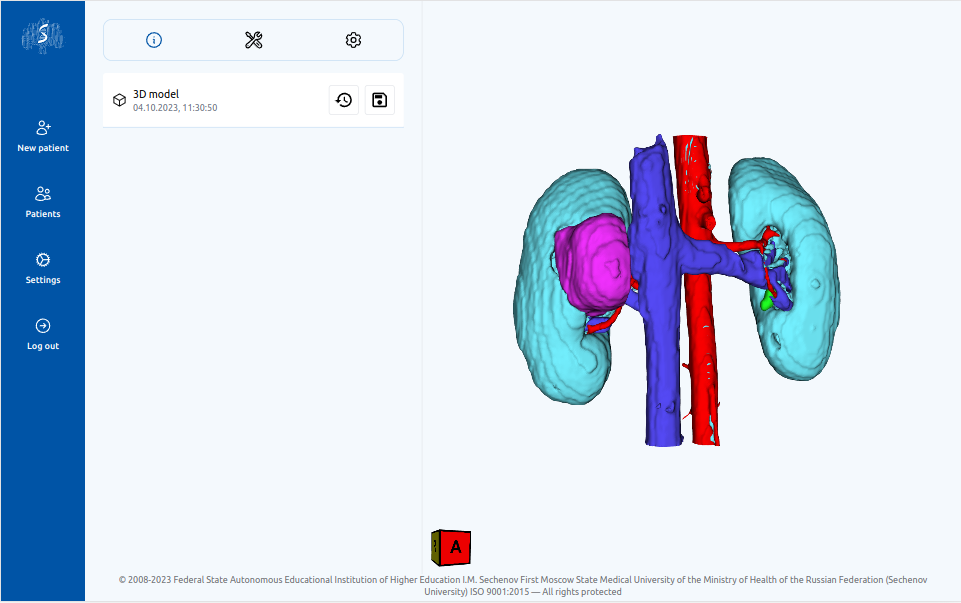

Преимущества 3д планирования

Персонализированная анатомия

Сервис позволяет выделить расположение артерий, вен, мочеточников, новообразований и паренхимы почки пациента.

4

Работа с 3D моделью

Врач может работать с 3D моделью для изучения анатомических особенностей пациента